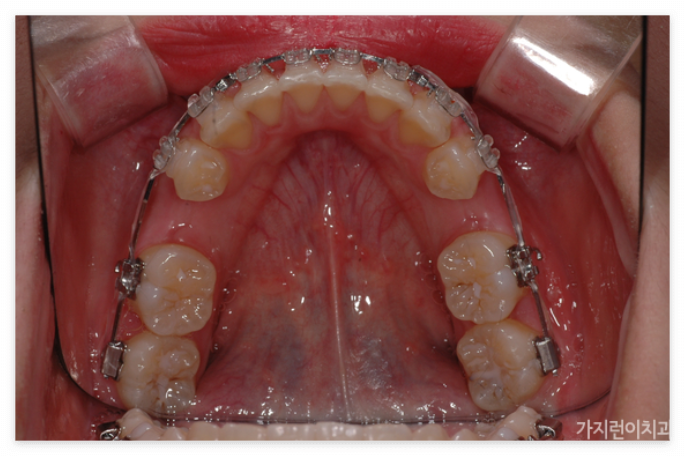

앞으로 돌출된 치아를 구조적으로 안쪽으로 집어넣기 위해서는 공간의 확보가 필요합니다. 그래서 많은 분들이 발치를 진행하는데요. 위와 같은 경우도 상하악 제1소구치를 발치한 후에 충분한 공간을 확보한 후에 진행을 하였습니다. 특히 발치가 무조건 안 좋고 비발치가 좋은 것이라고 오해하는 경우가 있는데 발치할 케이스임에도 비발치로 진행하게 되면 오히려 더 안 좋은 결과를 안아볼 수 있기 때문에 상악 전치의 후방이동을 위한 충분한 공간확보를 위한 과정이라고 이해하면 되겠습니다. 본원에서는 서울 거미스마일 교정을 위해 미니스크류를 식립해 상악 전치를 위로 올리는 힘을 추가 했습니다. 미니스크류를 이용하면 개선할 충분한 힘이 가해지기 때문에 상하악 전치가 동시에 이동할 수 있습니다.